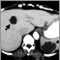

La poliquistosis renal y los quistes asociados en el hígado u otros órganos se pueden detectar con los siguientes exámenes: